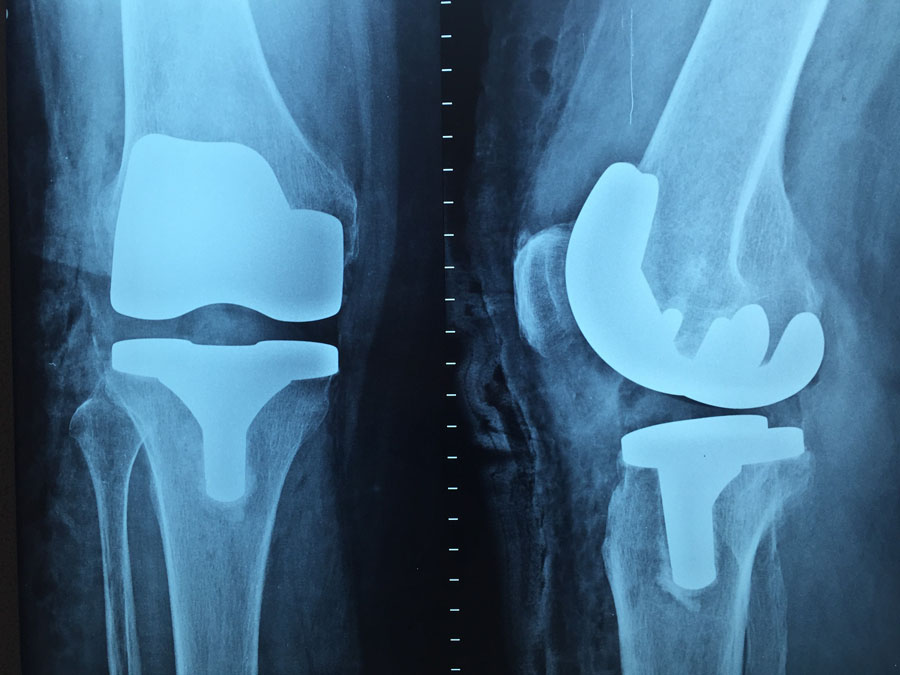

Napjainkban az ortopédia korrekciós műtétekkel, gyógyszeres terápiával, valamint fizioterápiás módszerekkel igyekszik javítani az ortopédiai betegek állapotán. Legyen szó arthrosisról, discus herniáról, valamilyen trauma miatt bekövetkezett, szalag, ín, izom, vagy porc problémáról.